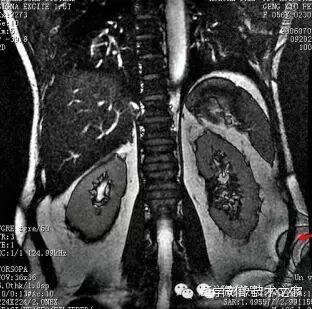

不同磁化率物质的交界面,磁化率不同会导致局部磁场环境的变形,造成自旋失相位,产生信号损失或错误描述。

在组织/空气和组织/脂肪界面(包括副鼻窦、颅底、蝶鞍等部位)出现异常信号。